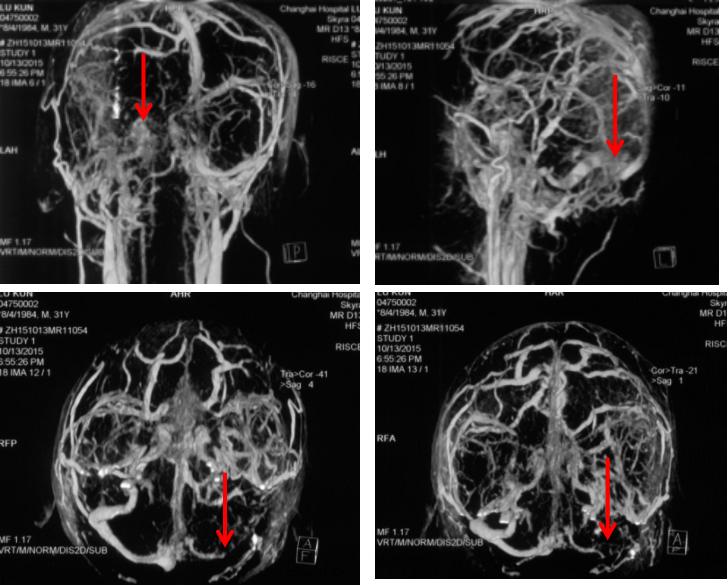

脑CTV:左侧横窦、乙状窦未显影;脑CTA:动脉未见明显异常,见图4

图4